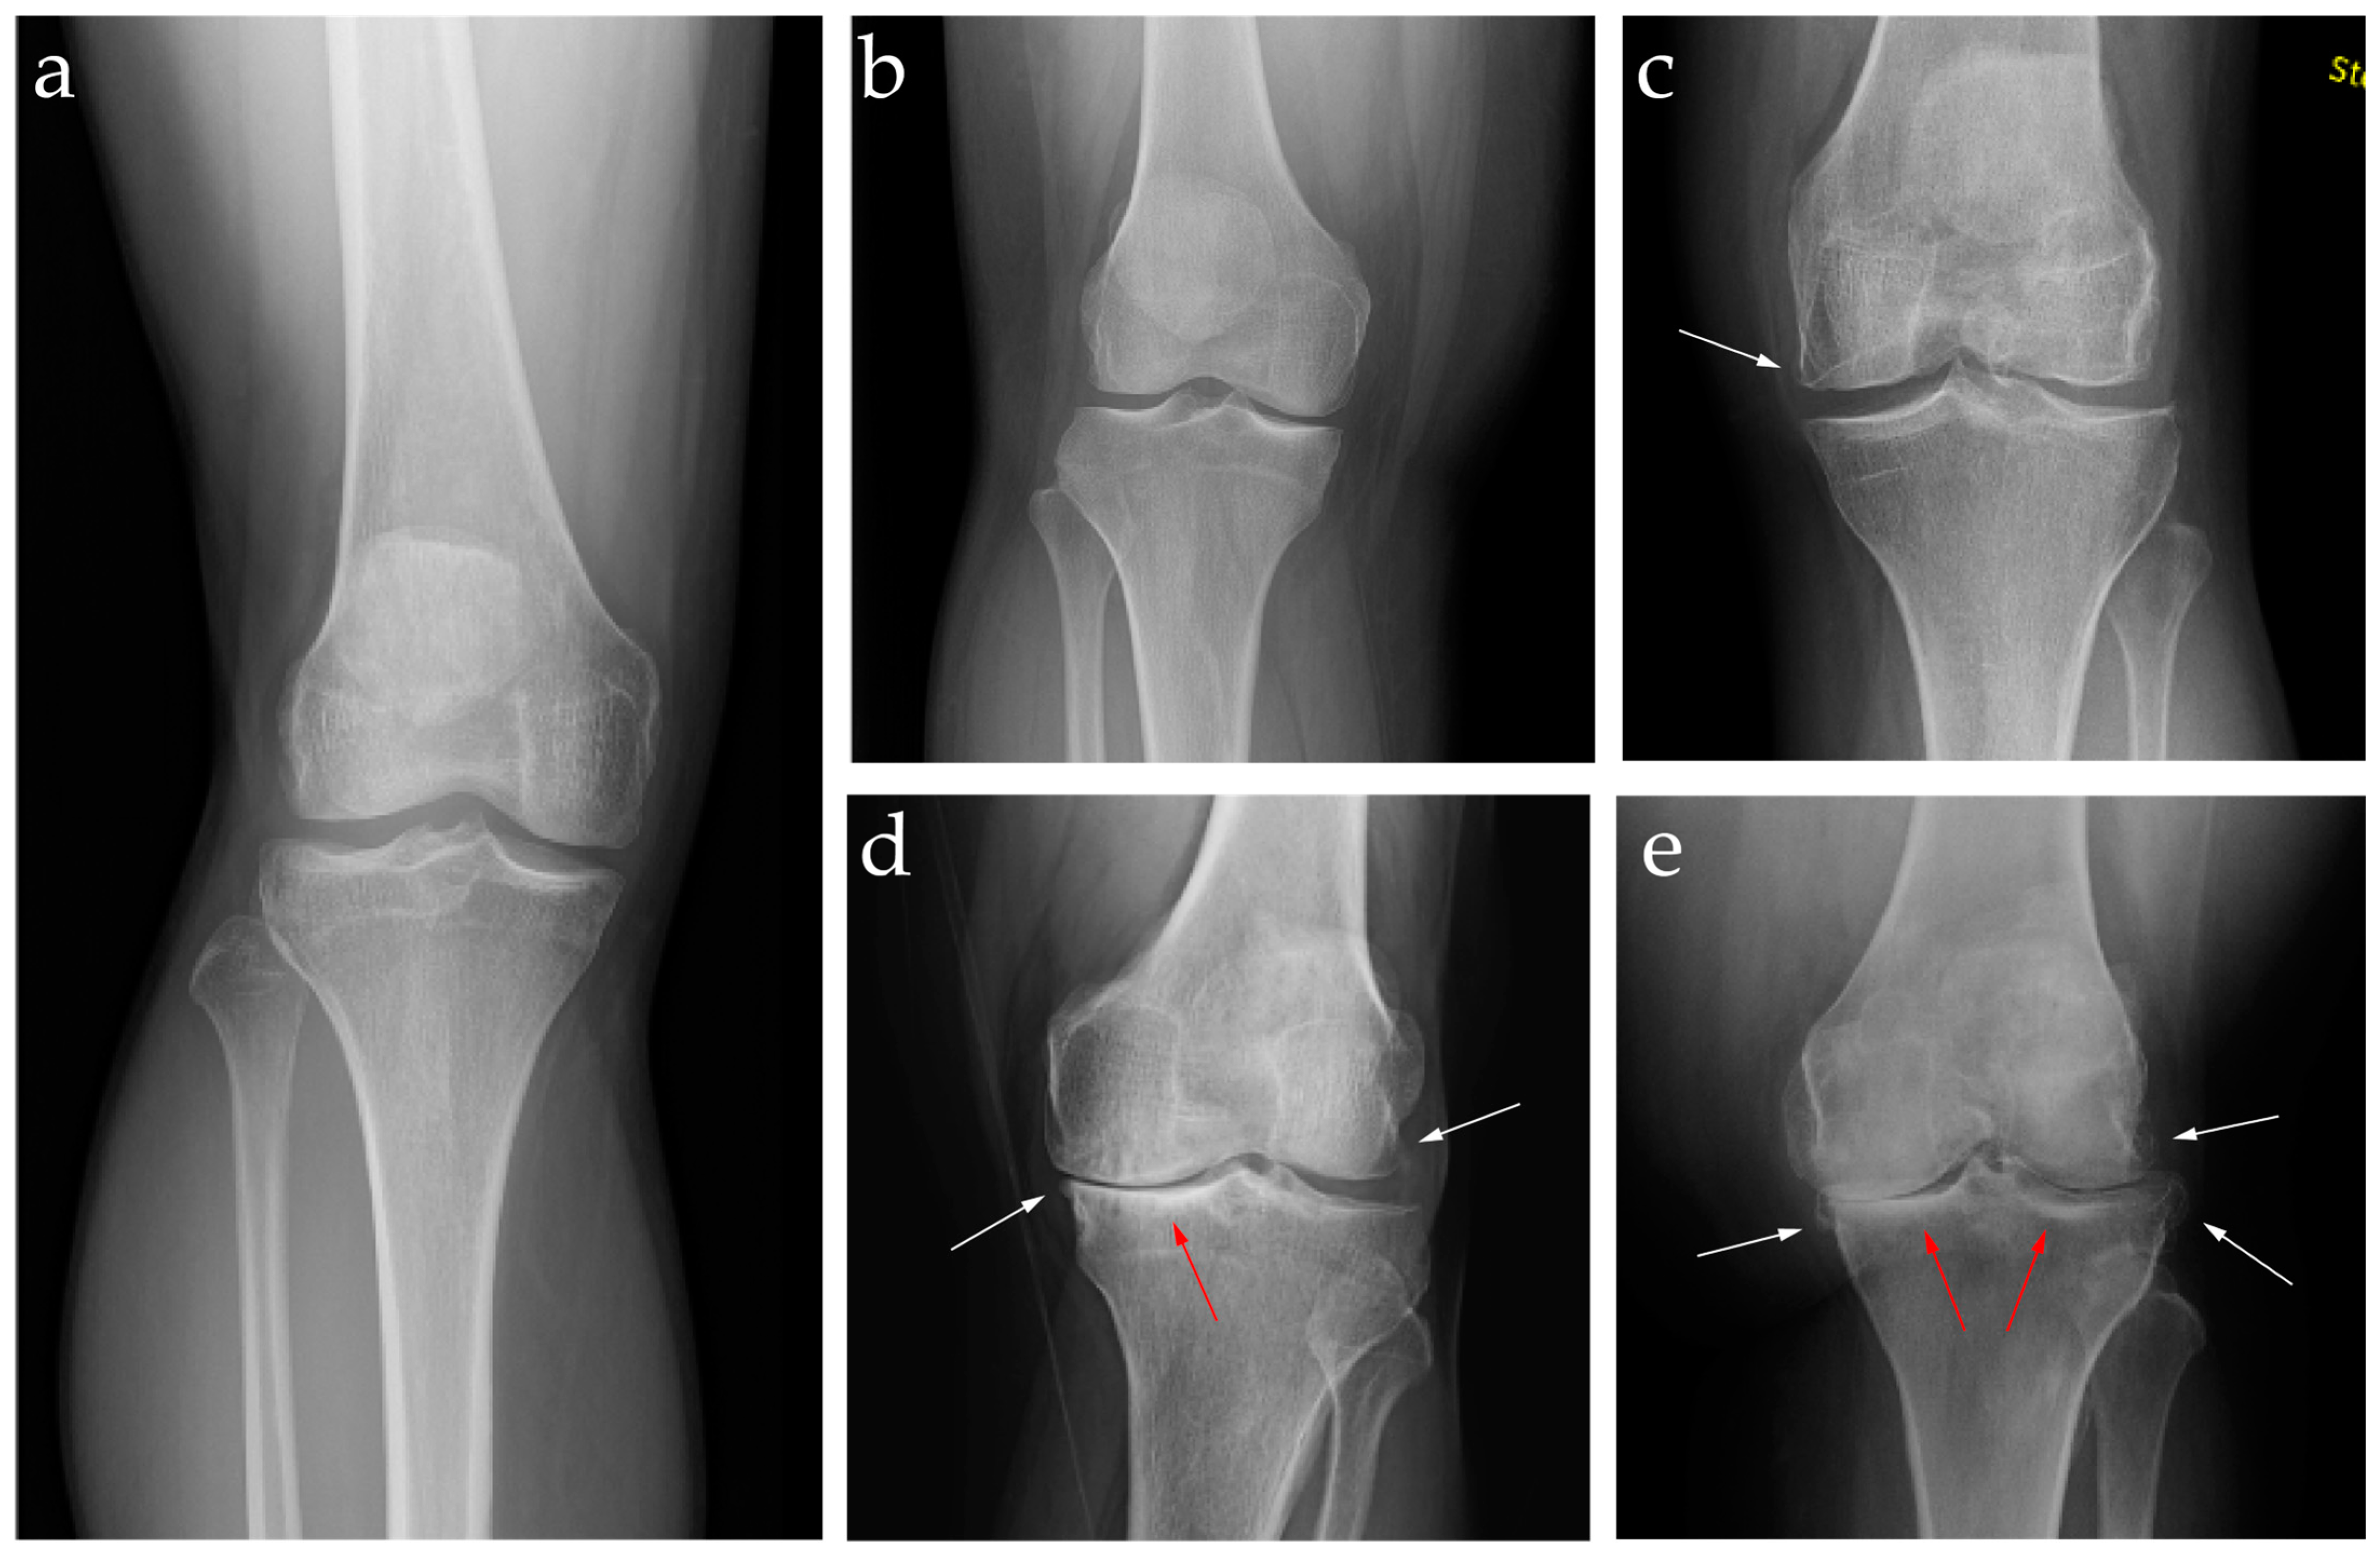

2.2. Diagnosis: Clinical Features and Image Findings

7.3. Genicular Artery Embolization Technique